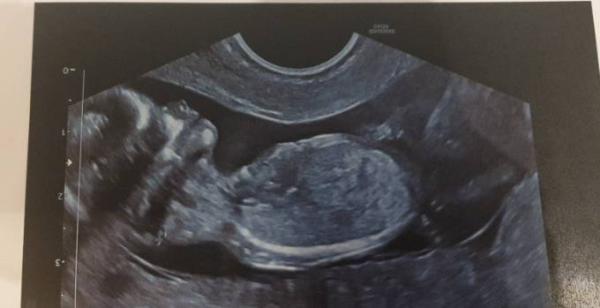

Hallo ihr Lieben, ich durfte heute auch nochmal zum Arzt. Es war sooo toll. Unser Krümel ließ sich richtig gut schallen, habe ganz tolle Bilder bekommen. Und riesig ist er, 6,3 cm schon. Ich bin eine Woche vordatiert worden und somit schon bei 12+3. Jetzt wird es offiziell. Ich freu mich soooo Euch allen ein schönes Weihnachtsfest und weiterhin alles Gute Liebe Grüße Claudi

Wow das ist wirklich ein tolles Bild Hab ein schönes Weihnachtsfest

Wow, ein tolles Bild . Und schon so groß- wundervoll . Weiterhin alles Gute und ein schönes Fest .

Wow, das Bild ist ja wirklich zauberhaft wünsche dir schöne Weihnachten

Sieht schon aus wie ein richtiges Baby. dann genießt mal euer Weihnachtsfest. :)